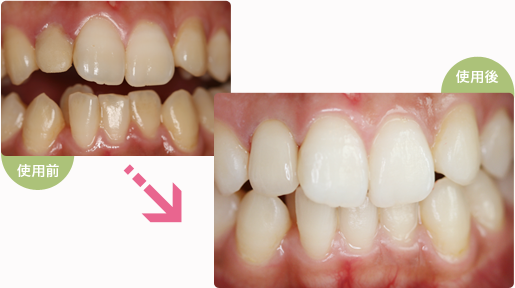

ホワイトニング

はつの歯科医院ではホームホワイトニングとオフィスホワイトニングを行っております。

ホームホワイトニング

1度来院していただき、ご自身の歯並びにあったマウスピースを作製します。

そのマウスピースに専用のジェルを適量流し、1日2時間程度マウスピースを装着していただくと約12日間で歯の白さがアップします。

オフィスホワイトニング

当院に来院していただき診療室で行うホワイトニングです。

1本から行うことが可能です。気になる部位をピンポイントで白くすることが可能です。

ホームホワイトニングと併用すると、より効果的です。